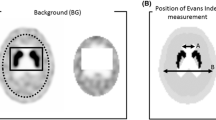

To investigate whether the FLB–CTV line could be used as an alternative reference for the AC–PC line, the angular differences between the AC–PC and FLB–CTV lines were measured on the midsagittal MRI scans created, using an angle measurement tool in the picture archiving and communication systems (PACS) monitor. This FLB–CTV line was defined as the one connecting the FLB and the point projecting to the more occipital side of the CTV (Fig. 1). While measuring the angular differences between the AC–PC and FLB–CTV lines, we noted that their values were relatively negative when the FLB–CTV line was set to the caudal side of the AC–PC line via the FLB coordinates. Additionally, we used Student’s t test to investigate whether there was a significant difference between the FLB–CTV line, which had shifted to the cranial and caudal sides against the AC–PC line. The AC–PC and the FLB–CTV lines of each patient were measured by a radiology technician with 13 years of experience in MRI.

Definitions of the AC–PC and FLB–CTV lines. The AC–PC line (double-headed blue arrowhead): the line connecting the AC and PC. The FLB–CTV line (double-headed red arrowhead): the line connecting the FLB and CTV. AC–PC anterior commissure–posterior commissure, FLB–CTV frontal lobe bottom and cerebellum tuber vermis